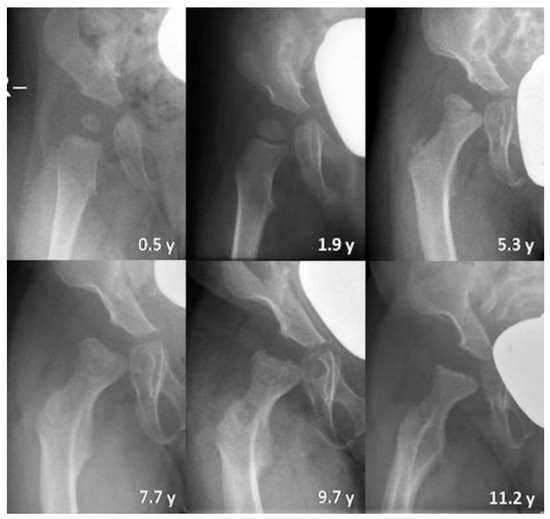

3.2.3. Qualitative Assessment of Radiographs